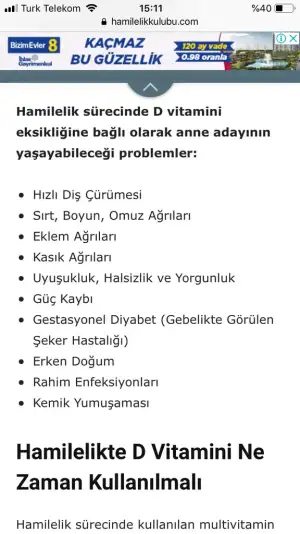

Cnm ben tesettürlü olduğum için güneşi vücuduma alabilmem mümkün olmuyo o yüzden de sürekli düşüyo takviye almam şart bi araştırma yaptım da ilk 3 aydan sonra kullanılabiliyormuş bugünden itibaren başlıyorum kullanmaya eksik olması halinde baya bi sağlık sorunu olabiliyormuş Allah korusunCanim ben de hamilelikten once kullaniyordum. Doktorum simdi kullanma dedi. Ilk baslarda kullanmamami soyledi. Belki de artık yaz geldi diye ertelemistir. Şimdi artik kritik donemi aştık sayilir. Doktorun verdiyse kullan bence. Icin rahat etmezse farkli eczacilara da sor. Gecmis olsun